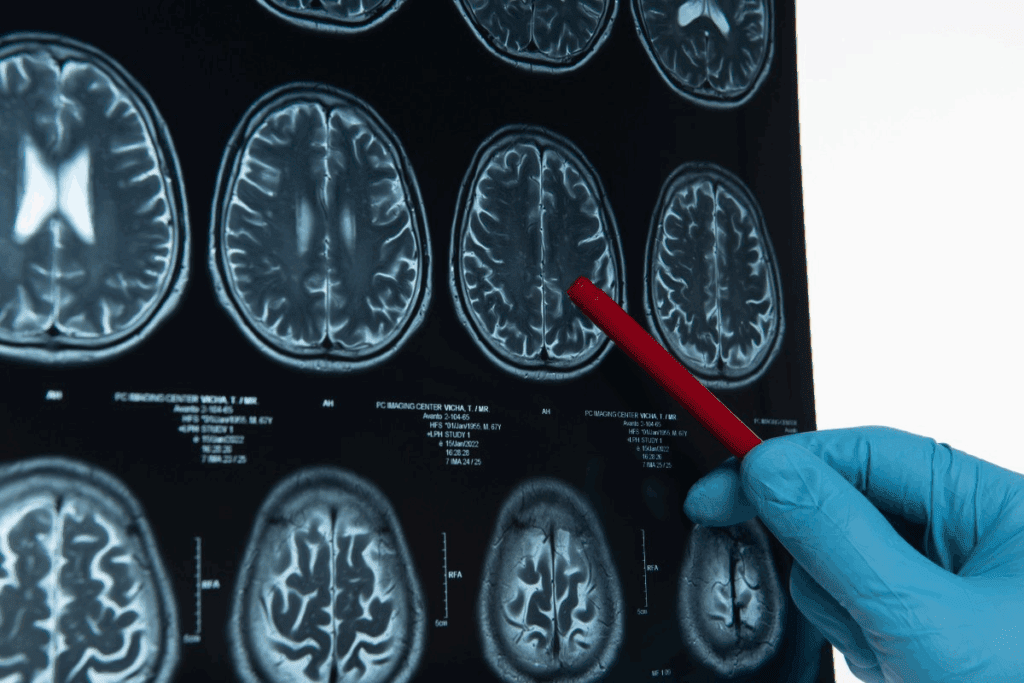

Imaging Techniques

Imaging is a big part of diagnosing cerebrovascular disease. CT scans and MRI scans are used to see the brain and its blood vessels. CT scans are fast and good for emergencies because they can spot bleeding right away.

MRI scans give detailed pictures of the brain. They help find areas where blood flow is low.